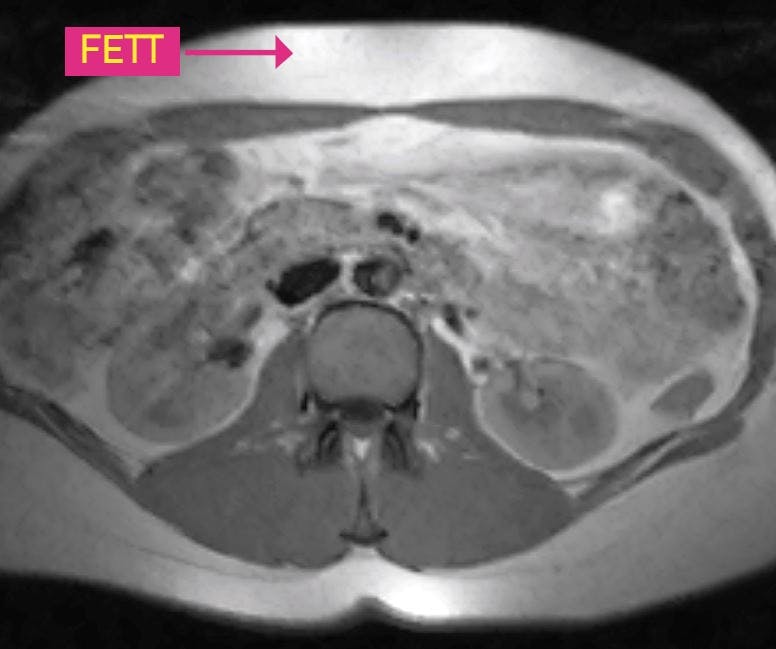

For mye mellom innvollene

FOR MYE MELLOM INNVOLLENE Tverrsnitt av mage. Denne personen har både mye magefett (det hvite) rett under huden og mellom innvollene.